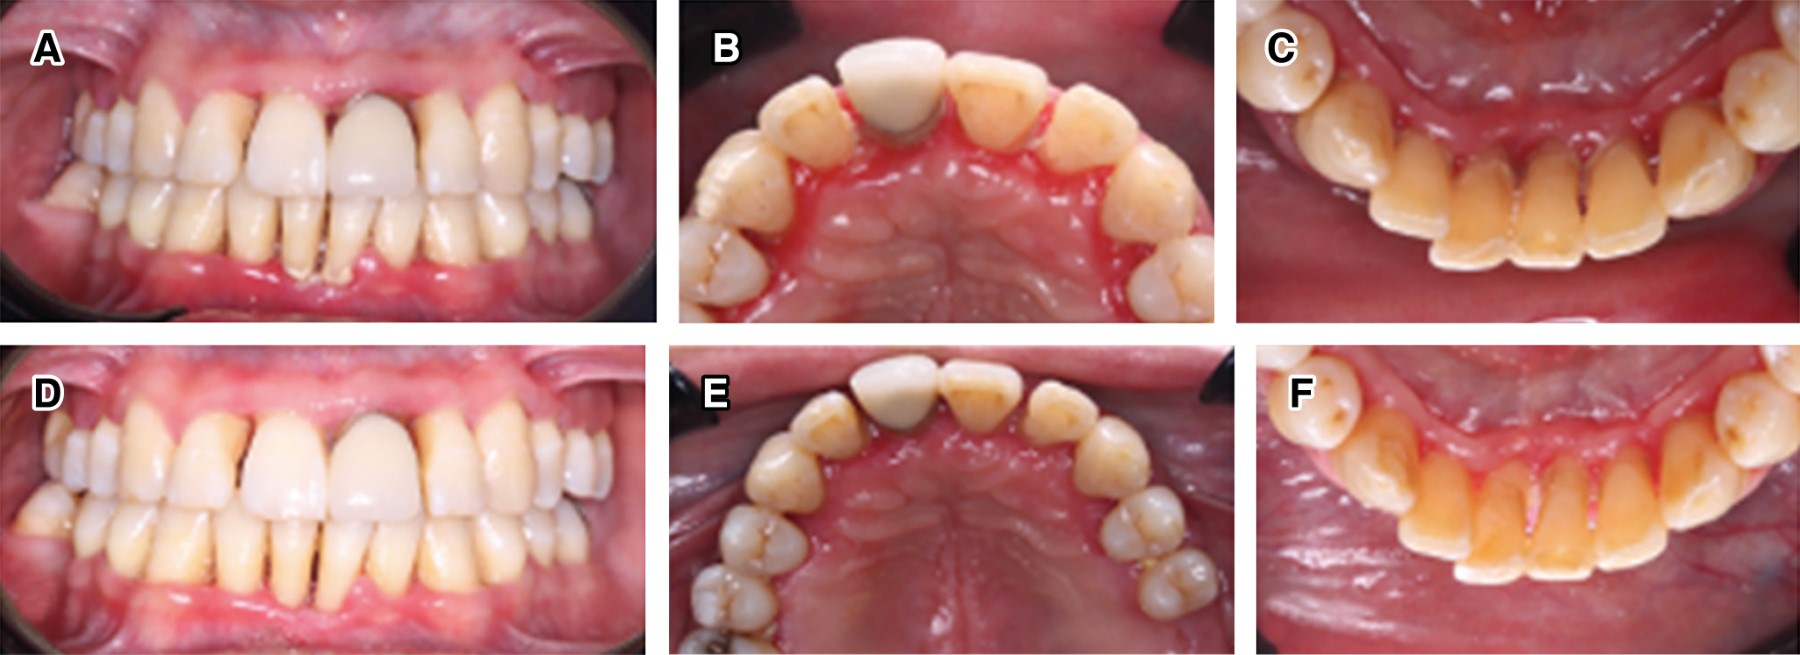

Figure 3